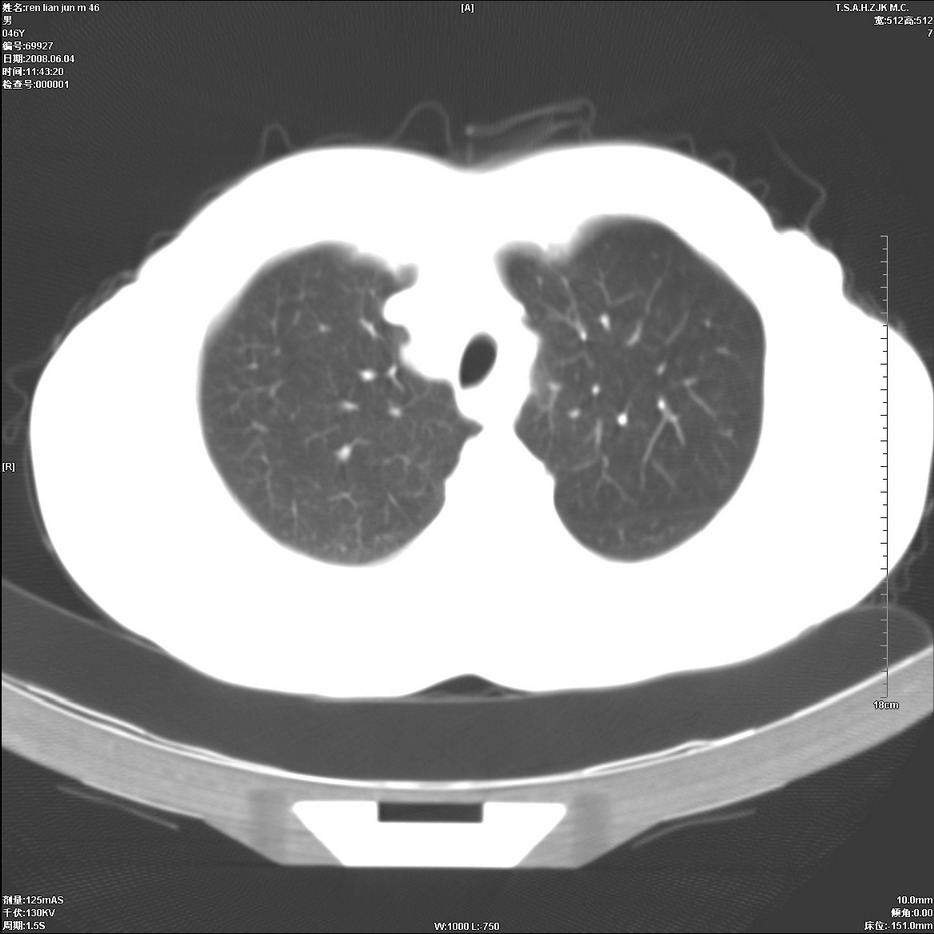

以下是引用qiu999在2008-6-5 17:14:00的发言:[br]考虑右肺中心型肺癌.颅内应做增强检查.

以下是引用形影不离在2008-6-5 19:18:00的发言:[br]右肺中心型肺癌并纵隔及左侧腋窝淋巴结转移,颅内应做增强检查。

以下是引用杀毒软件在2008-6-5 18:33:00的发言:[br]支持考虑右肺中心型肺癌,颅内病变是不是转移,不好说